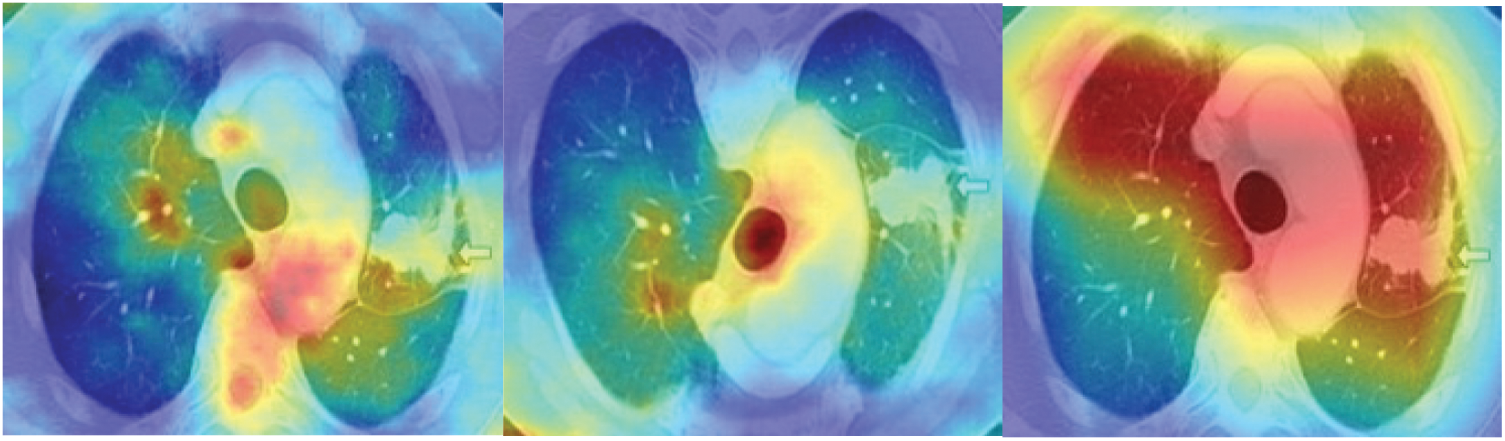

Fig. 4 shows the saliency maps of different stages of lung cancer CT scan images. After calculating the saliency maps, post processing techniques need to be adopted for refinement of segmentation images. Active contour methods [33] are used for the detection of cancer cells in the most consecutive image blocks. Also accurate separation of cancer cells from the other parts of CT scan images is badly needed, in order to give a precise output. Moreover, active contours are based on image intensity, which probably fails in differentiating the cancer cells. Additionally, these contour methods requires the higher computation time, which is considered to be serious problem in handling the larger datasets.

Figure 4: Sample CT images after applying the handcrafted saliency maps